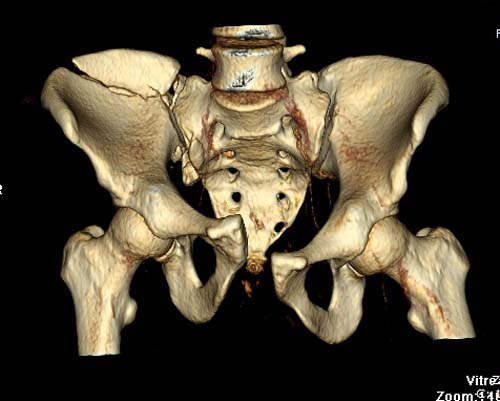

Перелом заднего отдела крыла подвдошной кости доказывает, что задние

связочные элементы подвздошно- крестцового сочленения интактны, и такой

перелом известен как“Сrescent fracture’. Переломы разделяется на 4 типа,

и до фиксации надо хорошо изучить топографию перелома, иначе винт может

попасть в линию перелома и не удержать фиксацию.

До операции желательно выставить все стандартные снимки: обзорный таза,

вход + выход. А популярный у всех 3Д используется только для общего

обзора, но не для детального изучения. Обычно КТ“для